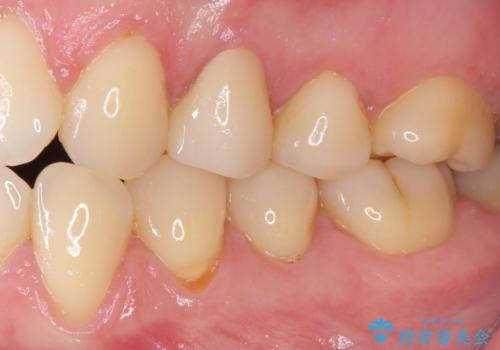

根管治療を行った奥歯は、再発防止や残された歯質を守るため、クラウンによる補綴治療が必要となります。

補綴後6ヶ月経過しレントゲンを撮影したところ、根尖周辺の病変が消失していることが確認できました。